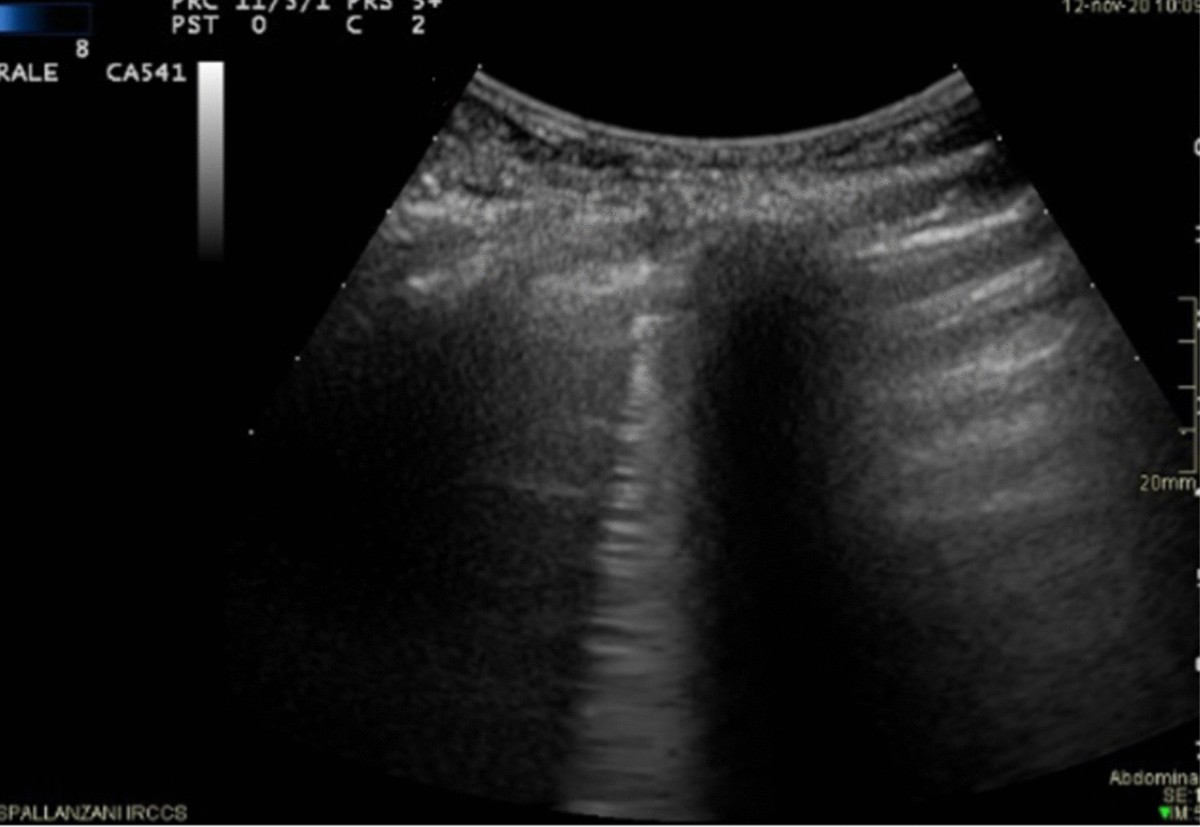

Qualitative and semi-quantitative ultrasound assessment in delta and Omicron Covid-19 patients: data from high volume reference center | Infectious Agents and Cancer